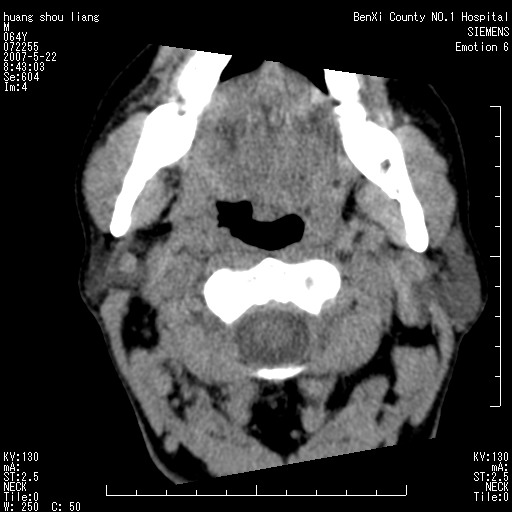

男性,64岁。颈部包块8年。最近增大。

对不起大家,可能是片子发太多有点乱,正常腮腺在下颌角的外侧,颌下腺在下颌体的中部内侧,本例在下颌角内侧偏下,和腺体一点关系都没有,从vrt和mpr上可以很明显看出来,再者肿块是好多粘连在一块的,大家在仔细看看,左侧可能也是吧,我还是考虑为肿大的淋巴结融合在一块,但性质??????

右侧腮腺下部均匀软组织密度肿块,外形不规则,与周围组织分界清晰,考虑右侧腮腺混合瘤或多形性腺瘤。

大家好,病理结果出来了,如大家所说,颌下腺混合瘤。

唉,解剖没学好吧,我诊断错了,不过还是有些不理解回去我在多看看书,谢谢大家的参与,以后我还会奉献好的病例。